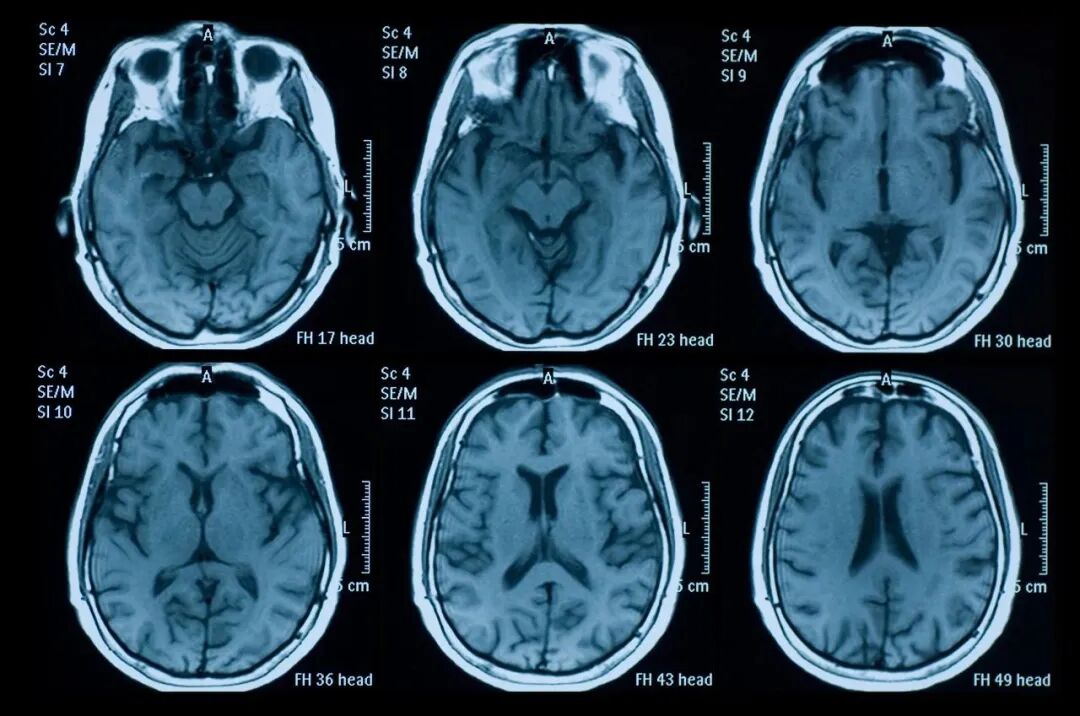

阿尔茨海默病(Alzheimer sdisease, AD)是发生在老年期及老年前期,以进行性认知功能障碍和精神行为症状为特征的神经系统退行性病变,是痴呆最常见的病因,约占老年期痴呆的50%~70%。

阿尔茨海默病是大脑中认知和执行功能的改变——意味着您回忆事实、记忆和信息的能力受到损害,做出决定的能力也受到损害。

从本质上来讲,是指大脑变得不专心了。因此,患者会以茫然的方式凝视,这也许是大脑中所谓“缠结”的早期信号。